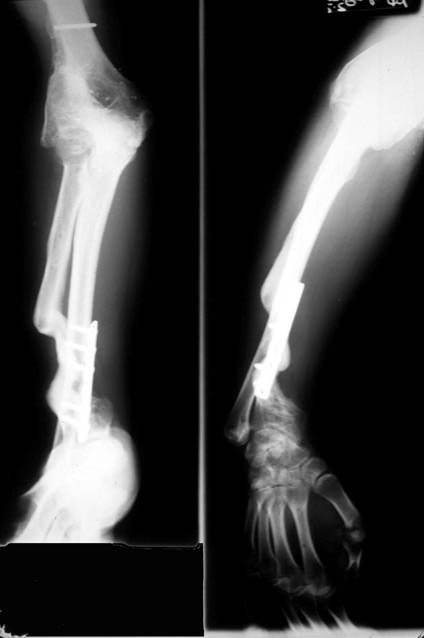

E.R. is a 26 year old male lifeguard who had a severe, unfortunate accident the first time he ever mounted a motorcycle. He was in a coma for many months with head trauma and had fractured his right elbow and forearm at the time of injury. He developed a condition called Heterotopic Ossification which meant that multiple joints “froze-up” due to deposits of calcium in the joint capsules. He was not able to walk until both hips were operated on by an internationally known hip surgeon who then referred him to Dr. Badia to address the stiff Right elbow and deformed forearm. In fact, at the initial visit, the patient stated that he had not moved the right elbow AT ALL for nearly 4 years and was unable to feed or groom himself with that hand. After a series of 3 operations to reconstruct both the elbow and forearm, this young man has gone back to swimming, work and a normal lifestyle.

The pictures depict the application of the dynamic external fixator, which stabilized and provided early motion to the rigid elbow after aggressive release of the capsule and bone excision.